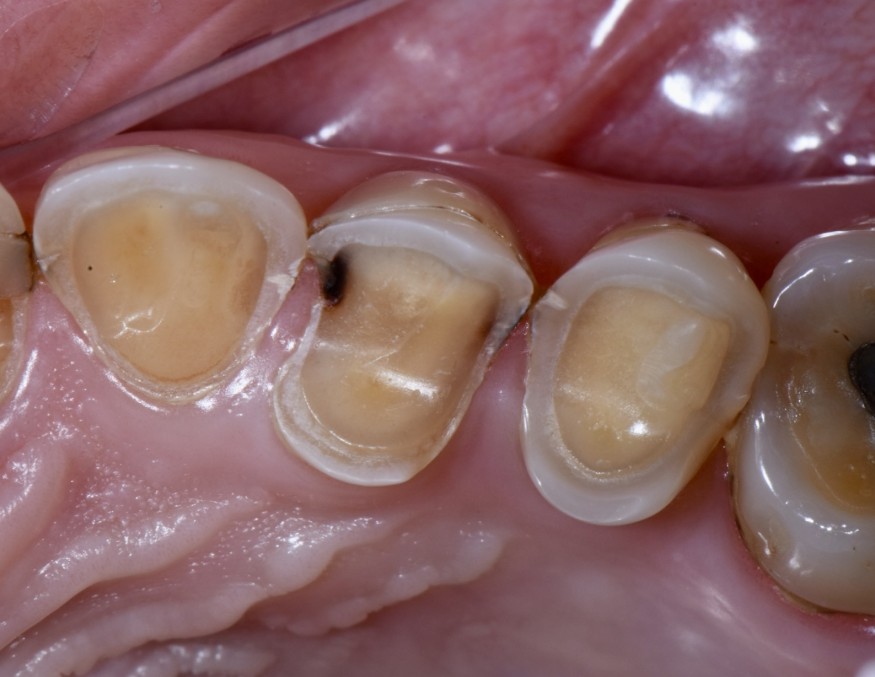

- Exposition dentinaire, due à la perte d’émail ou de cément, par abrasion (brossage traumatique), érosion (acides), attrition (bruxisme) (fig. 3-7), ou anomalies de structure (MIH**, amélogenèse imparfaite) [5].

(Crédit photo : Olivia Kérourédan) - Figure 5. Association de lésions d’usure d’origine érosive, abrasive et attritionnelle.

(Crédit photo : Olivia Kérourédan) - Figure 6. Lésions d’usure typiques provoquées par des phénomènes d’abrasion.